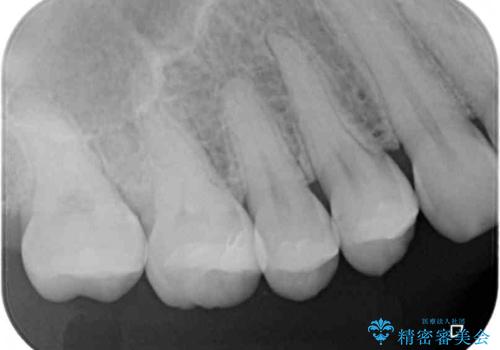

土台の材料を外して顕微鏡下で確認したところ、歯根にまで及ぶ破折が認められたため、インプラント治療を行うこととしました。

他にも銀歯や欠損となっている歯に対しての治療も希望されたため、補綴治療を行うこととしました。

インプラント治療をきっかけに、銀歯を全てセラミックに替えていきました。